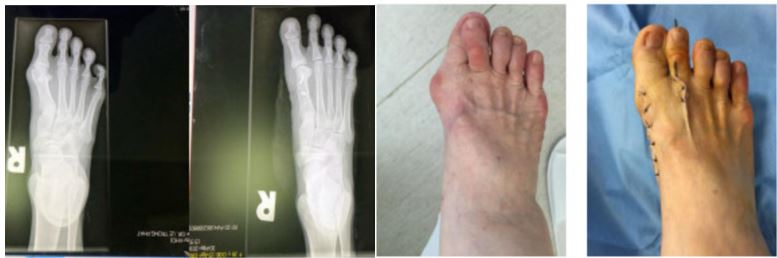

MRI Imaging and Clinical Photos Before and After Hallux Valgus Surgery at FV Hospital

According to Dr Phat, the foot contains more than 200 ligaments and tendons, making it an exceptionally complex structure. Therefore, if treated incorrectly, patients may risk losing the ability to walk. Treating foot conditions requires meticulous care and the expertise of specialists. There are over 130 surgical methods worldwide for treating this condition, with the Chevron, Lapidus, and Scarf procedures considered the most effective. The Lapidus and Scarf surgeries are recommended for more severe cases. In particular, the Scarf procedure – a challenging technique – has been shown to achieve a 92% satisfaction rate among patients. At FV Hospital, Dr Phat regularly performs this surgery, with no complications reported.